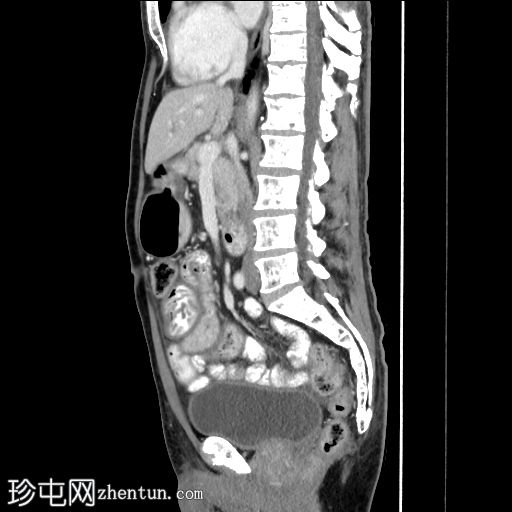

轴向C+门静脉期

矢状C+门静脉期

十二指肠和空肠皱襞弥漫性低衰减结节性增大增厚,

造影剂(阳性)增强。微量腹水。

左侧少量积液,伴轻度胸膜增厚。良性肾脾囊肿。骨髓异质性。

这是酪氨酸激酶抑制剂 (TKI) 相关小肠淋巴管扩张的典型表现,是癌症再分期时需要注意的独特副作用。此类药物可导致小肠和大肠淋巴管扩张,从而引起胃肠道症状。